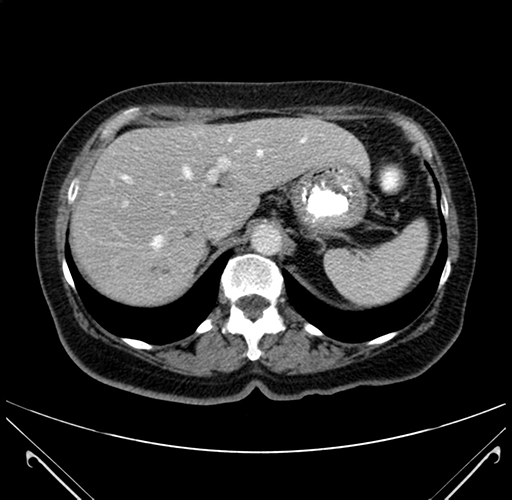

Pre-Chemo: Axial Venous